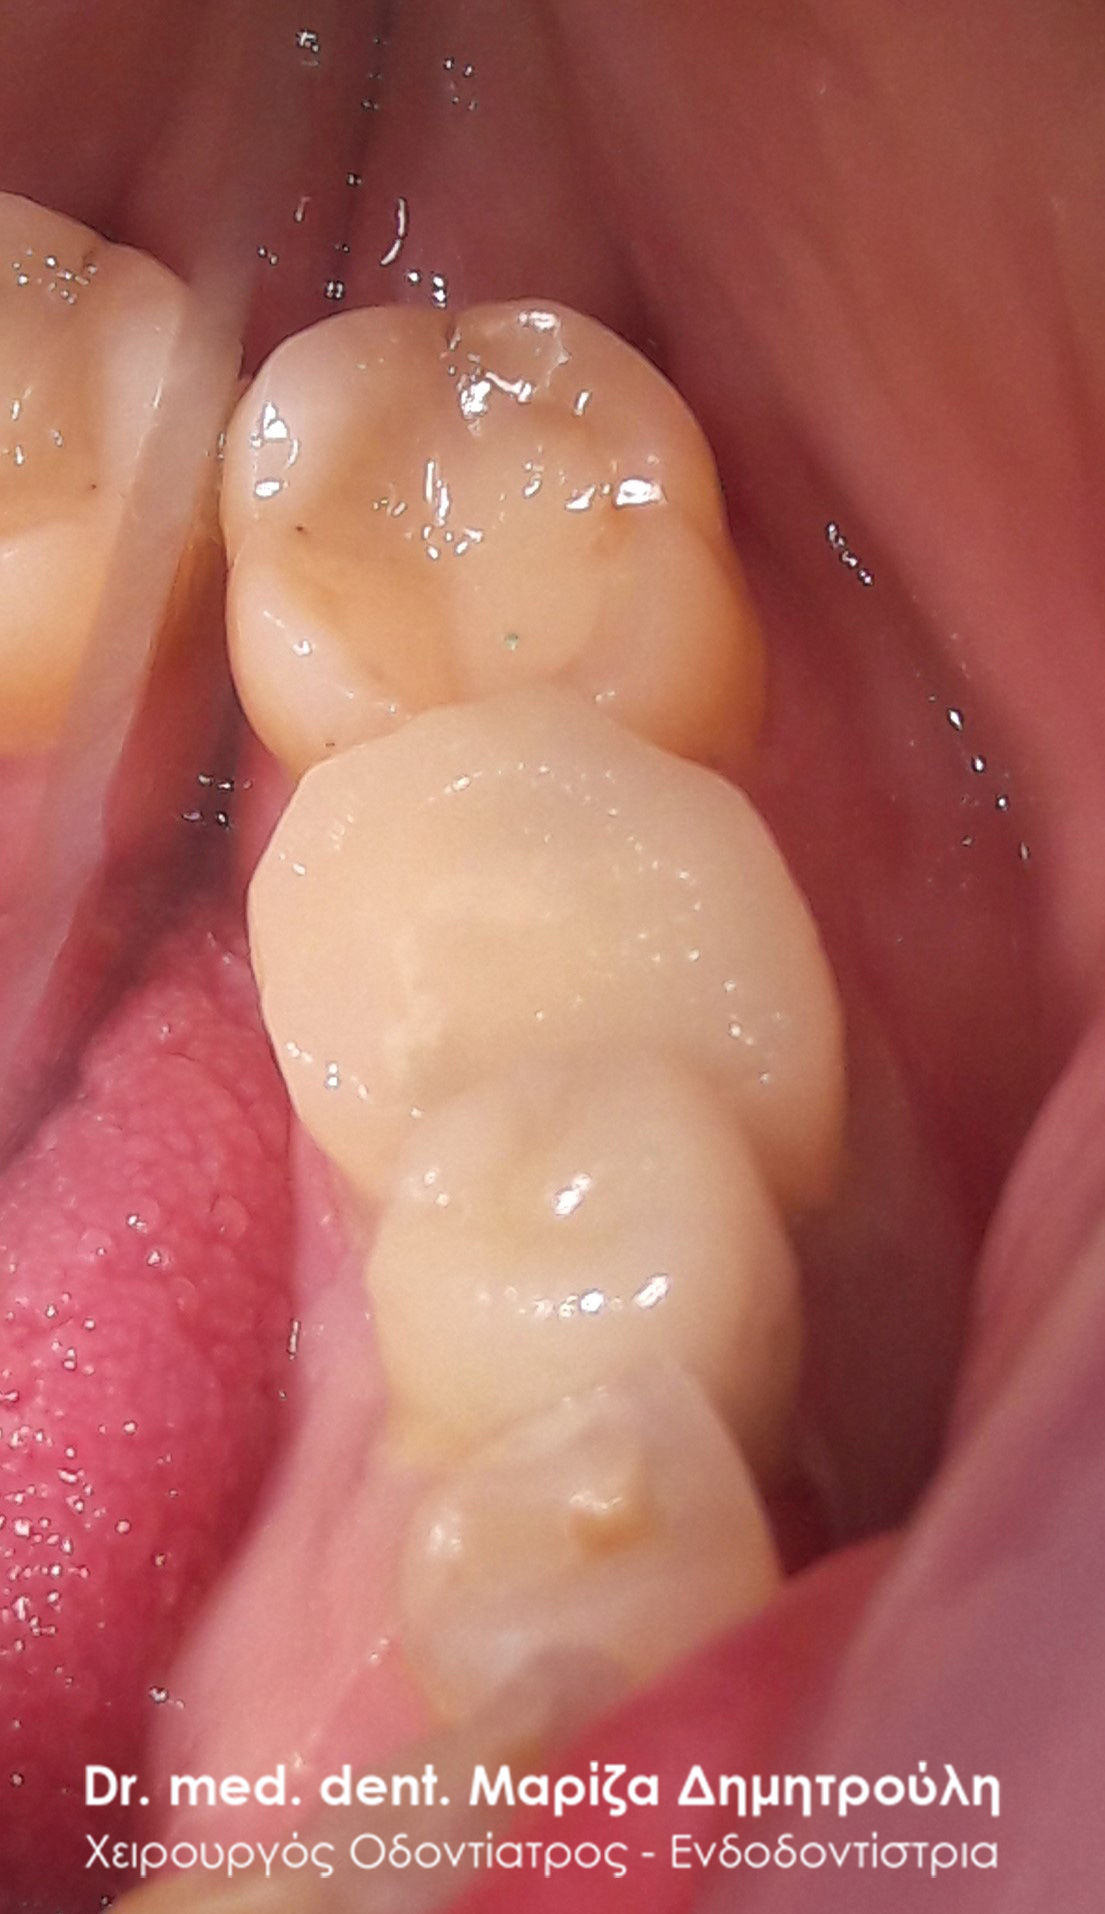

Εικόνα του δοντιού πριν τη λήψη αποτυπώματος

Τελική κλινική εικόνα του ολοκεραμικού ένθετου στον προγόμφιο